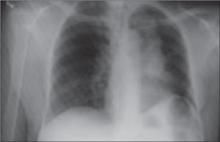

His right foot was boggy, swollen, and tender with significant crepitus. Brownish discharge was oozing from the sole of his foot (FIGURE 1). There were large infected subcutaneous bullae on the dorsum of his foot (FIGURE 2). We could feel a popliteal pulse in both legs, but could not feel a right dorsalis pedis pulse.

Late clinical signs of necrotizing fasciitis include cellulitis, skin discoloration, discharge of “dishwater” fluid, blistering, and hemorrhagic bullae. Findings of crepitus and soft tissue air on plain radiographs are seen in 37% and 57% of patients, respectively.4 Our patient’s X-ray findings revealed extensive gas pockets within soft tissue and osteomyelitis changes of the 5th metatarsal head.